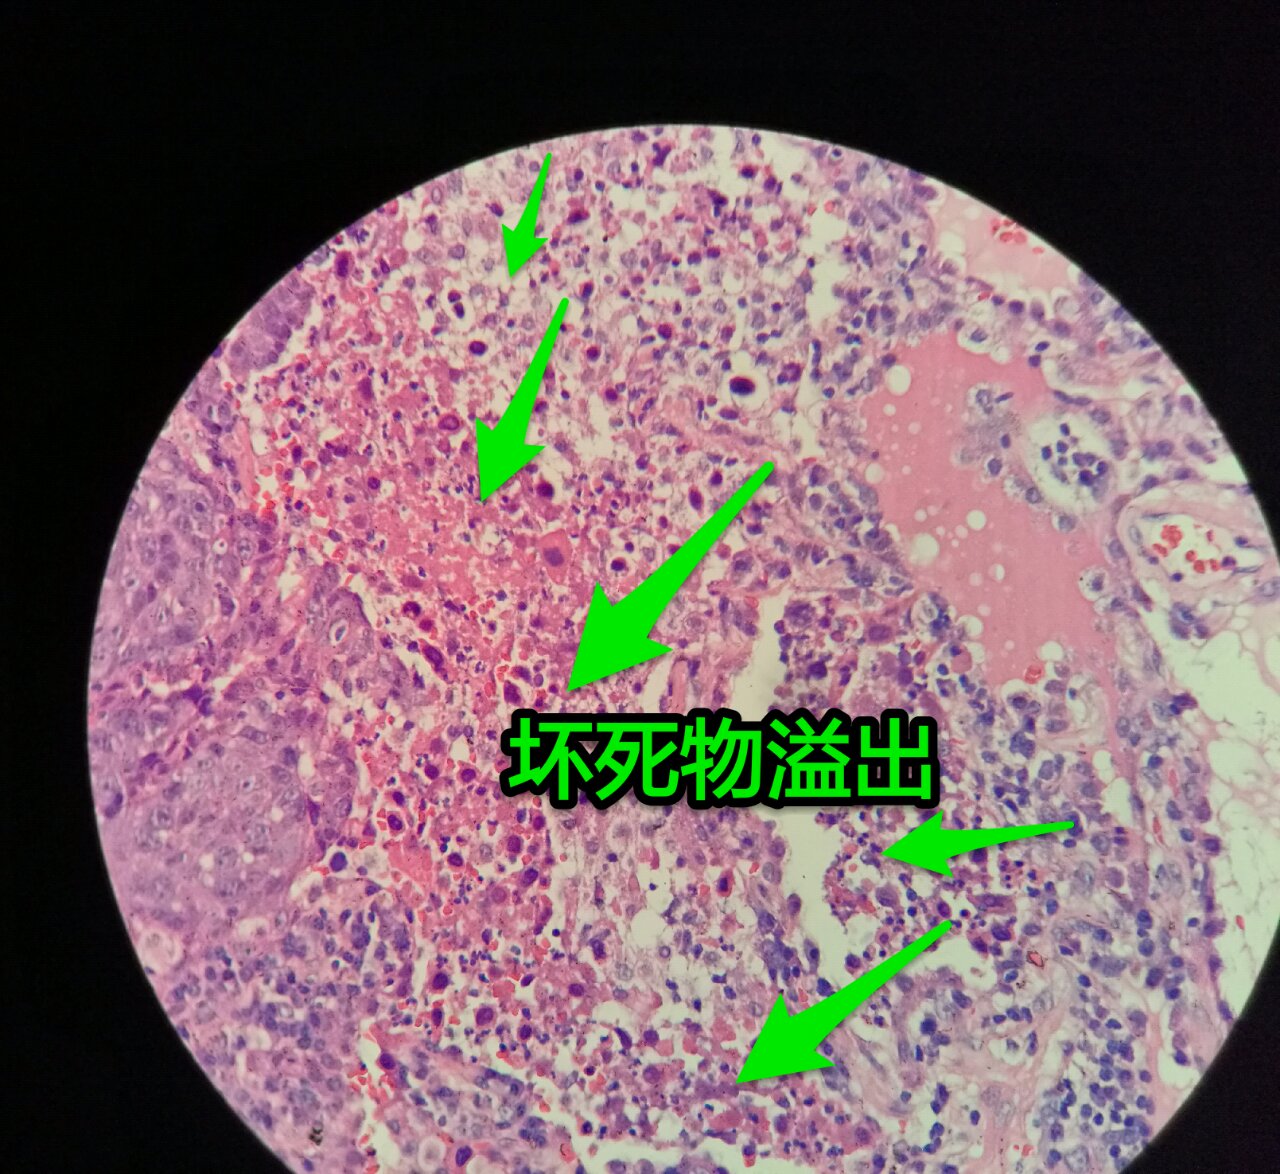

这个鳞癌不是早期

坏死也可以很大

较大的粉红区都是坏死,可以看出坏死是因为巢团大,中央坏死

下图是放大

左手边有一点鳞癌,右手边有正常肺泡组织,中间有坏死物,这是为什么呢?

坏死物质渗出。

并且可以有吞噬,坏死物里常有血液成分

剖面多呈黄色

肿瘤周围不应是缺血,坏死一般在巢团内